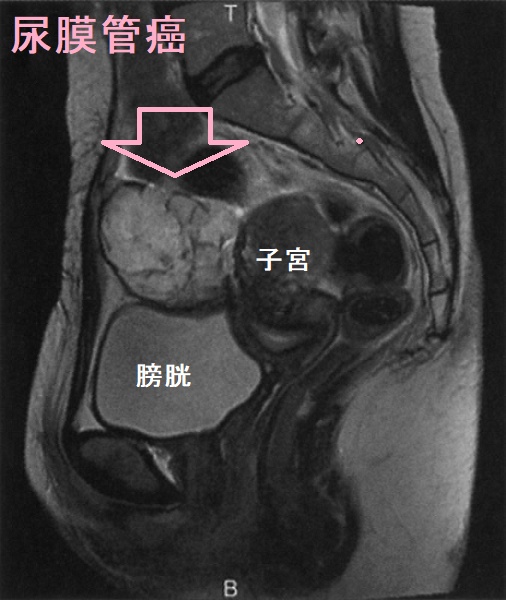

尿膜管遺残(尿膜管嚢胞)は、尿膜管癌になる場合もあります。尿膜管癌は膀胱粘膜下腫瘤で、頻尿症状などから見つかります。